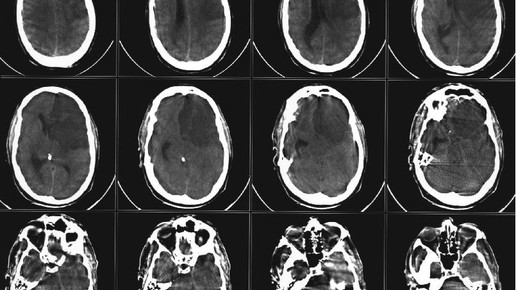

Beim Thema Schlafanfall denken viele nur an Ältere. Doch auch junge Menschen kann es treffen. „Der Lebensstil hat viel damit zu tun, dass auch Jüngere zu Patienten werden“, sagt Dr. Bettina Begerow von der Deutschen Schlaganfall-Hilfe. Sie nennt Bewegungsmangel, Nikotin, Überernährung und Stress als Faktoren. Doch wie können Jüngere erkennen, ob sie möglicherweise ein Schlaganfallrisiko haben?

Plötzliche Lähmungen, ein hängender Mundwinkel, motorische Einschränkungen oder Sprachstörungen können auf einen Schlafanfall hindeuten. „Einige Patienten sind nicht mehr in der Lage, Sätze zu formulieren oder die richtigen Worte zu finden“, sagt Begerow.

Manche Patienten haben der Expertin zufolge beim Laufen das Gefühl, ins Leere zu treten, wieder andere haben Drehschwindel, fühlen sich also wie in einem Karussell. Auch halbseitige Lähmungen – etwa im Gesicht oder am Arm – können vorkommen.